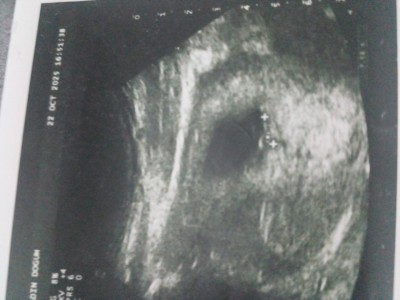

Kızlar 7+3gunluk ultrason göruntusu keseye gore cinsiyet tahmini yaparmisiniz kizlar

Gebelik haftası 7+3

Ramzi teorisi var internette sizde bakabilirsiniz. Sağ altta ise kız diyor sizinkide öyle gibi. Benim kızımda da aşağıdaydı tutmuştu yani bu teori